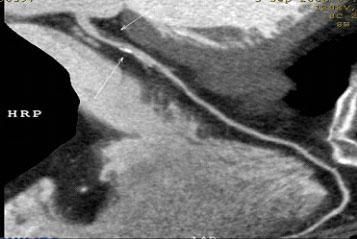

二、多層螺旋CT頭頸部及體部血管成像技術:

該機掃描覆蓋範圍廣、時間短,多種後處理分析軟件能顯示各血管細小分支,可以清晰顯示動脈瘤、動脈夾層、血管畸形、血管狹窄及動脈粥樣硬化斑塊等,适用于頭頸部血管成像、肺動脈成像、胸腹部血管成像及四肢血管成像。